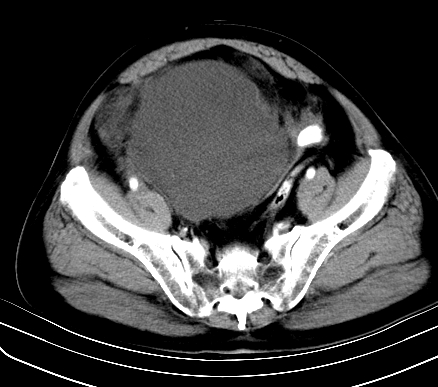

标题: CT19729B:男,74岁,因腿疼就诊,查体触腹部肿物,

增强扫描

延时期

重建

【ct表现】

1、肿块巨大,往往位于腹膜后,长大后才引起症状而就诊;那么位于腹膜后的肿瘤80%为恶性肿瘤。

2、实性肿瘤,增强扫描轻度不均强化,实性肿瘤一般不是好东西。

3、肿瘤边缘似见少许脂肪样密度。

4、腹膜后未见肿大淋巴结,但肿瘤于临近的肠管及组织接触紧密。

【诊断】

腹部占位,考虑位于腹膜后的恶性肿瘤,脂肪肉瘤(实体型)可能性大。

术后病理结果:腹膜后脂肪肉瘤。